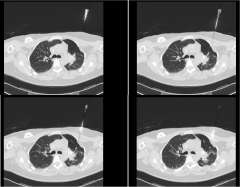

The second row shows images (axial, coronal, and sagittal) of the distribution of the radiation dose that was delivered to this area. One can see that the dose of radiation to this target is very tightly distributed to avoid as much normal tissue as possible.

SBRT requires highly accurate, precise, and focused radiation delivery in order to be successful because of the high dose of the treatment and the rapid radiation dose drop-off. It utilizes the same principles that have allowed radiation oncologists and neurosurgeons to successfully deliver highly focused and precise radiation treatment to brain tumors and brain metastases. Unlike the CNS, however, tumors and organs throughout the body can potentially move with breathing and other factors. SBRT treatments require accurate and precise tumor localization at the time of radiation simulation (Figure 4). Our expert team works closely with our interventional radiologists or surgeons to place fiducials (tiny gold seeds, or coils) into a patient's tumor in as minimally invasive a way as possible. These fiducials act as localizing and tracking devices (Figure 5). Fiducials assist us in targeting the tumor more accurately and precisely. The placement of fiducials is a procedure much like obtaining a biopsy for the tissue diagnosis of the cancer and is safely performed under image-guidance.

SBRT requires accurate and custom mapping for each individual patient's anatomy and organ motion so that we may be able to optimally target the tumor and simultaneously spare the surrounding normal tissue. We utilize any and all potential imaging modalities such as PET, MRI, CT, as well as other novel imaging platforms to localize the tumor in four dimensions. It requires highly sophisticated radiation delivery systems not available in most radiation oncology practices. More importantly, it requires clinical expertise and experience which allow our expert radiation oncologists to make sound treatment judgments regarding a recommendation for SBRT. In addition, you can be assured that our expert team will competently follow-through with an efficacious and safe SBRT radiation plan at the time of treatment. Instead of several weeks of conventional radiation therapy, patients complete their SBRT in a short-period of time, usually over a one week period, minimizing the inconvenience of daily trips to the radiation oncology facility.